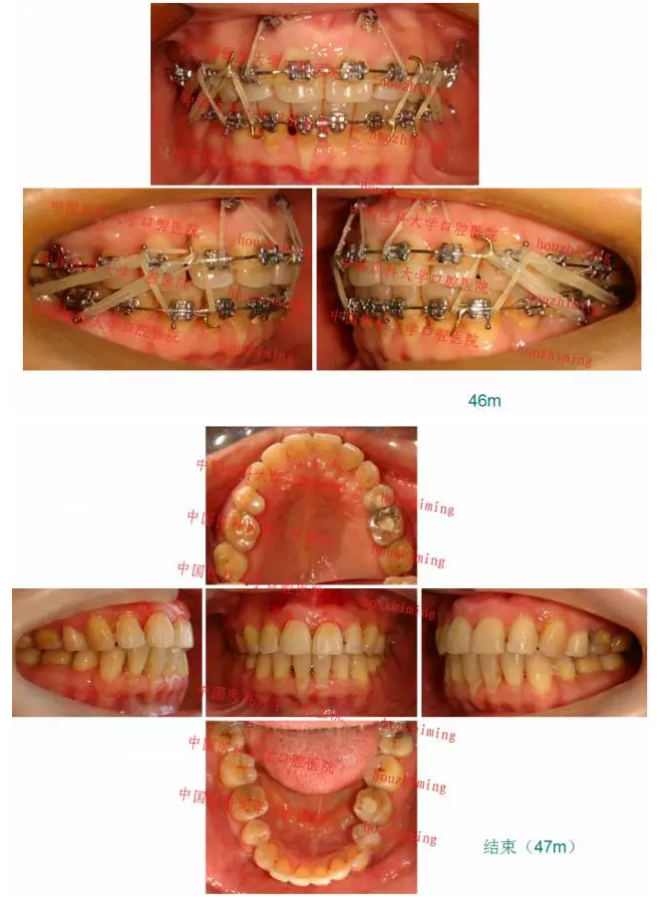

【原創(chuàng)博客】這樣的代償矯治大家滿(mǎn)意嗎?(重度骨性二類(lèi))——侯志明

轉(zhuǎn):侯志明 愛(ài)齒-KQ88口腔醫(yī)學(xué)